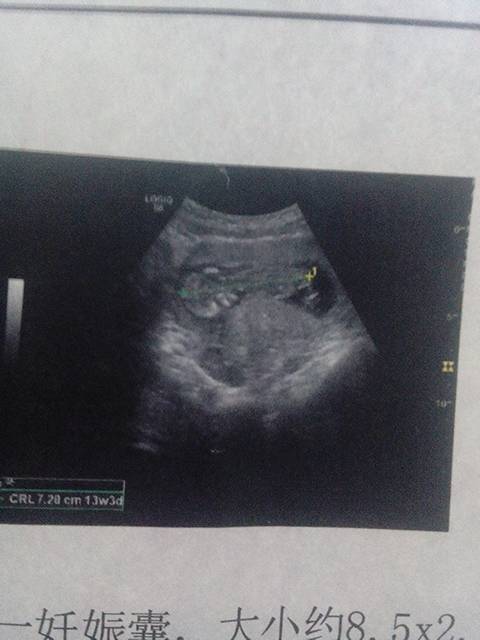

今天去检查子宫前位,宫体增大,宫内见一妊娠囊,大小约8.5x2.9cm,内见一成形胎儿,胎心胎动好

今天去检查子宫前位,宫体增大,宫内见一妊娠囊,大小约8.5x2.9cm,内见一成形胎儿,胎心胎动好,CRL:7.3cm    ,结果是不是胎儿发育很好呀?,是男孩还是女孩呀,